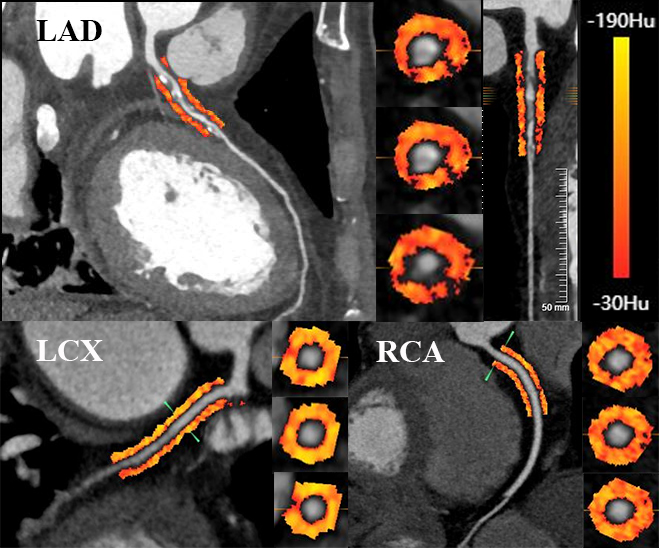

All reconstructed CCTA data were transferred to semi-automated post-processing software (United Imaging Intelligence, version R001, United Imaging Healthcare Co., Shanghai, China) for pericoronary FAI analysis. According to the landmark study by Antonopoulos et al. [15], pericoronary FAI was defined as the mean CT attenuation of coronary PVAT from –190 to –30 HUs, and coronary PVAT was defined as the adipose tissue located adjoining the coronary artery at a distance equal to the diameter of the vessel. To measure pericoronary FAI, the PVAT located in the proximal 40-mm segments of three major coronary arteries (LAD, LCX, and RCA), were traced and analyzed as previously described [20]. Notably, for LAD and LCX, the proximal 40-mm segments were analyzed, while for RCA, the proximal 10- to 50-mm segments were analyzed to avoid the interference of aortic wall on the most proximal 10-mm segments [20]. An example of pericoronary FAI analysis is shown in Fig. 2. To evaluate the reproducibility, FAI values were analyzed by two experienced radiologists who were blind to clinical data.

Fig. 2.Example of the color-coded quantitative analysis of pericoronary FAI surrounding the proximal LAD, LCX, and RCA. FAI, fat attenuation index; LAD, left anterior descending artery; LCX, left circumflex artery; RCA, right coronary artery; HU, Hounsfield unit.